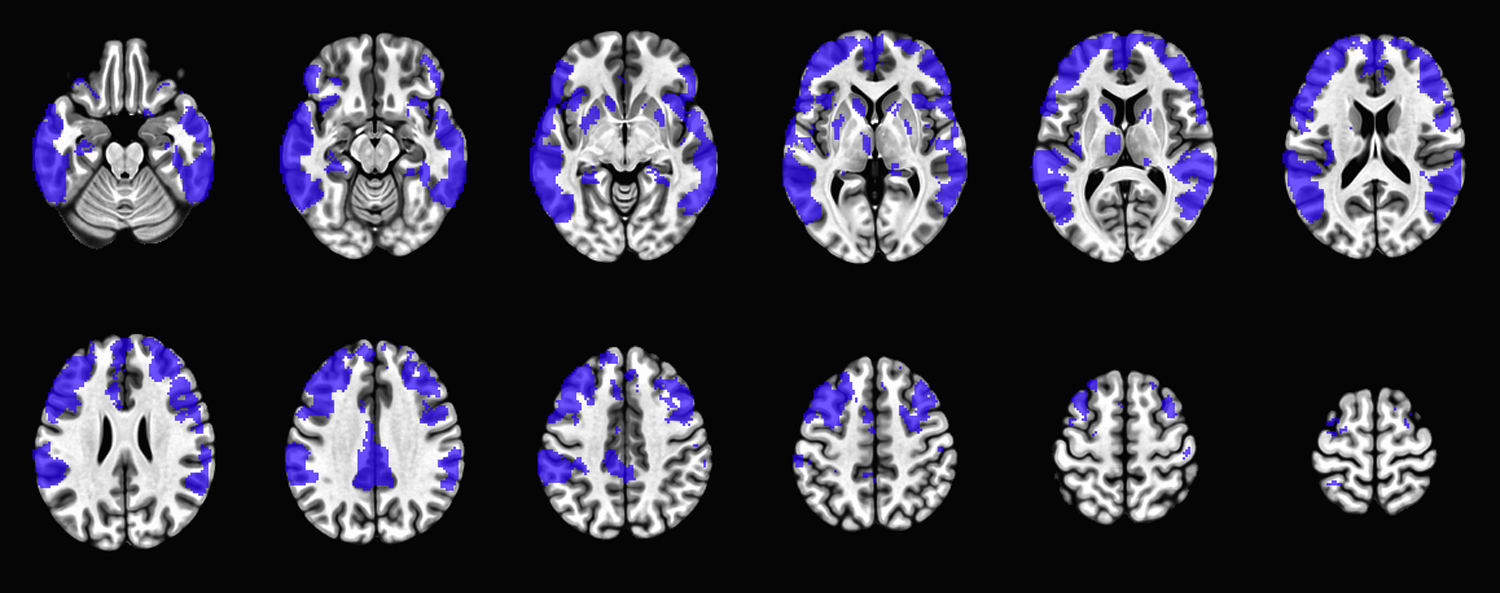

Abstract Image